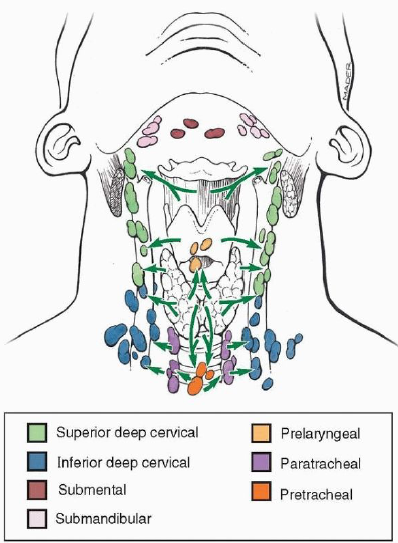

Lymphatic system

總圖

Nodes

Lingual Lymphatic nodes

病灶

Groups

- Level I

- the submental group (Ia), and the

submandibular group (Ib). - Level II

- the upper jugular lymph nodes

- level IIa – CN XI 前

- level IIb – CN XI 後

- Level III

- the middle jugular lymph nodes

- Level IV

- the lower jugular lymph nodes

- Level V

- all lymph nodes contained within the posterior triangle

- Level VI

- lymph nodes of the anterior (central) neck compartment

Tip

清除 I, II, III

Nasal cavity

Oral cavity

Tongue

Tonsil

Waldeyer’s tonsillar ring

Larynx

用vocal fold 分,上,下分別到SDC, IDC

Thyroid

跟著Sup./ Inf. thyroid a.走,分別到SDC, IDC

Nose